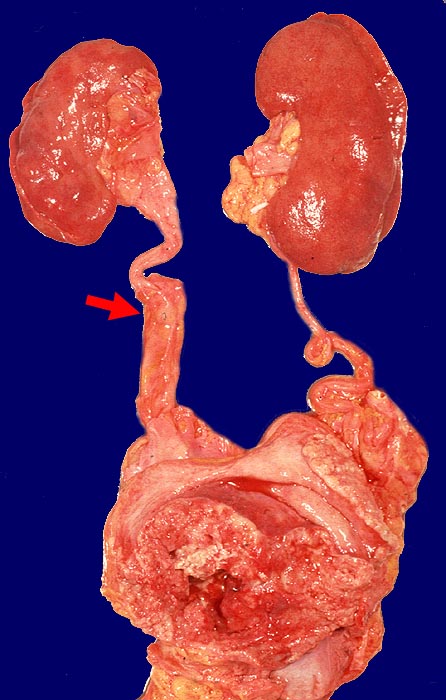

Polypöses Harnblasenkarzinom

Polypöser Tumor der Harnblase. Tumorstenose des rechten Ureters distal mit geringgradigem Hydroureter rechts.

Wenig differenziertes Urothelkarzinom. Tumordurchmesser 10cm. Infiltration des perivesikalen Fettgewebes mit vesikovaginaler Fistelbildung.

St.n. mehrfacher transurethraler Blasenresektion